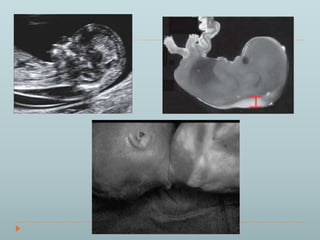

 Numerical – (Polyploidy) Triploidy

69,XXY; 69,XXX; 69,XYY (3N)

• Miscarriages (2nd or 1st trimester)

• Fetus: variable, growth, MCA (renal, cardiac,

cns, sex), dysmorphism, assymmetry (mosaic),

developmental delay

• Paternal origin of extra set cause:

Placental abnormality (partial molar)